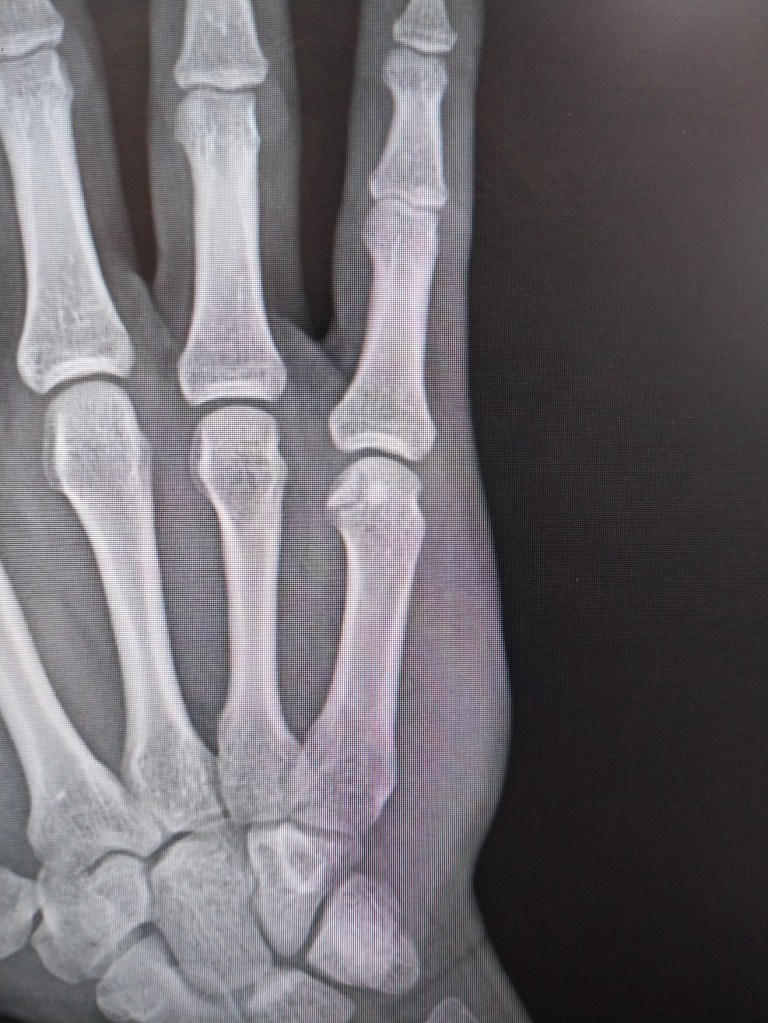

Yes, he is now in Casper Wyoming and thrilled to be near some mountains and more civilization. Right after he arrived, however, he broke his hand playing basketball and has had to wear a splint.